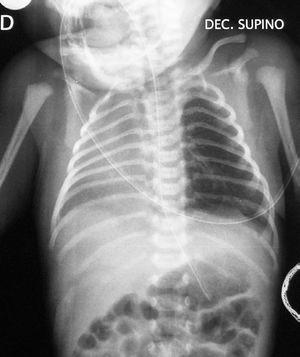

Con este cuadro clínico, ante la presencia de dificultad respiratoria inmediata y desplazamiento del latido hacia la derecha, se realiza radiografía de tórax urgente (fig. 1) apreciándose una opacificación en hemitórax derecho, sin visualizarse claramente la silueta cardíaca, no objetivándose neumotórax. El pulmón izquierdo parece mostrar una hiperinsuflación compensadora. Se realizan además: hemograma: normal. Gasometría capilar: mínima acidosis respiratoria. Hemocultivo: negativo. Ecografías abdominal y craneal: normales. Ecocardiografía: situs solitus. Dextroposición con levoápex, comunicación interauricular amplia con cortocircuito izquierda-derecha, comunicación interventricular perimembranosa de 4-5 mm tapada por tejido accesorio de la válvula tricúspide, ductus arterioso persistente con cortocircuito izquierda-derecha. Cariotipo: masculino normal (46XY).

Figura 1. Radiografía simple de tórax: opacificación de hemitórax derecho. Hiperinsuflación compensadora de pulmón izquierdo. No evidencia de aire ectópico.